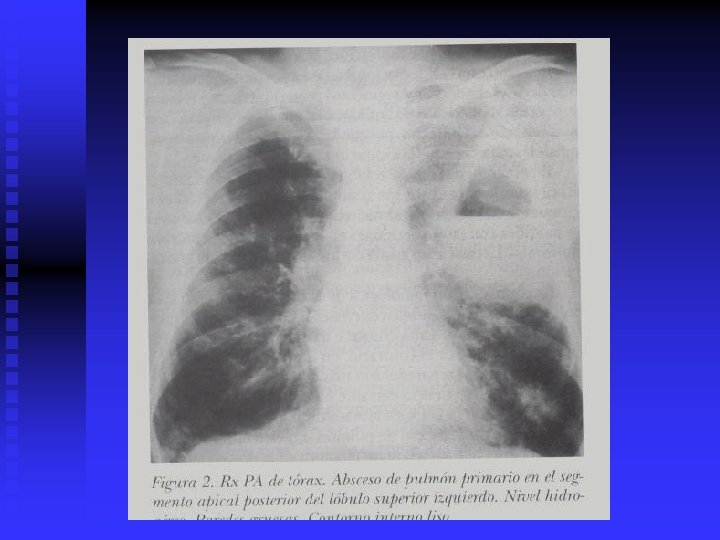

Absceso Pulmonar n DIAGNÓSTICO. n CLINICO. Neumonía, septicemia RADIOLOGICO. Rx. PA y lateral, TAC. BACTERIOLOGICO: Frotis Gram. Cultivos ENDOSCÓPICO O PUNCIÓN n n n n TRATAMIENTO. Antibióticos múltiples. 6 a 8 semanas Inhaloterapia y Fisioterapia del tórax Broncoscopía para drenaje Drenaje quirúrgico y resección